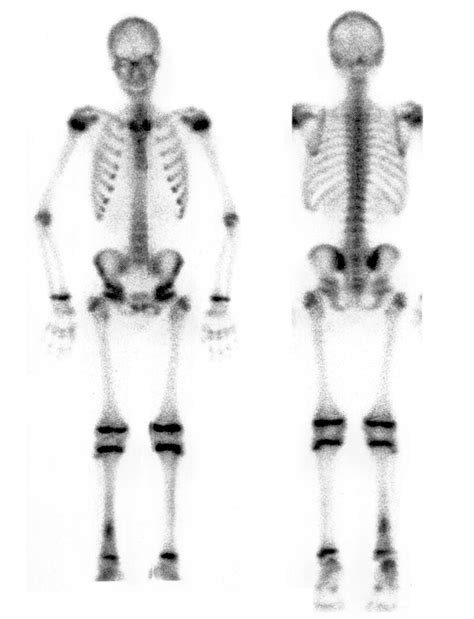

Una delle applicazioni più cruciali della scintigrafia ossea è nella diagnosi e stadiazione dei tumori ossei, sia primari (benigni o maligni) che secondari (metastasi). Le metastasi ossee, lesioni tumorali secondarie originate da tumori localizzati in altri organi, sono frequentemente rilevate grazie all'aumentato metabolismo nelle aree interessate. La scintigrafia ossea total body, che acquisisce immagini dell'intero scheletro, è particolarmente utile per identificare la presenza e l'estensione di queste lesioni, fornendo informazioni fondamentali per la pianificazione terapeutica.